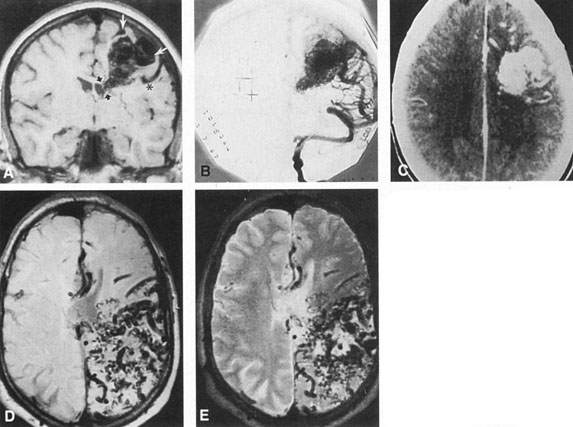

The detection of intracranial AVMs is facilitated by CT scanning and MRI (Fig. 10),88 but optimal management requires selective angiography89 that assesses the size and configuration of the mass, the number and location of feeding arteries, the flow characteristics and degree of steal from brain parenchyma, and the pattern of venous drainage.

Fig. 10. Neuroimaging of arteriovenous malformation. A: Coronal magnetic resonance imaging (MRI) (TR, 600 ms; TE, 20 ms) shows wedge-shaped vascular mass extending from the surface of the parietal cortex (white arrows) to the lateral ventricle (black arrows; asterisk, arterial feeder). B: Posteroanterior left arteriogram of the same lesion. C: Axial computed tomography scan with contrast enhancement. D: Axial MRI of a large arteriovenous malformation, first echo (TR, 2000 ms; TE, 20 ms). E: Second echo (TR, 2000 ms; TE, 90 ms). (From Smith HJ, Strother CM, Kikuchi Y, et al: MR imaging in the management of supratentorial intracranial AVMS. AJNR Am J Neuroradiol 9:225, 1988.)